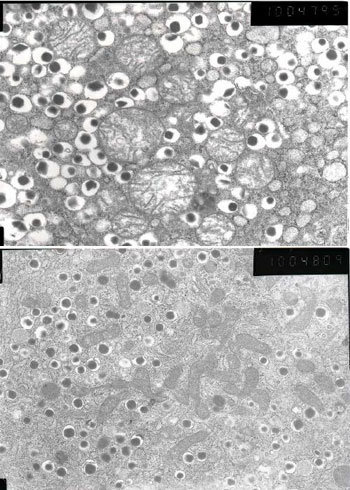

結果幼鼠出生時處於營養失調狀態,體重比正常白鼠低20%左右。斷奶後,即使喂以正常飼料,體重也不太容易增長。在出生20周之後,研究組分解了這只幼鼠的胰腺,通過電子顯微鏡進行了觀察。出生20周的鼠,相當於20、30多歲的人。

觀察結果顯示,分泌胰島素的β細胞明顯變小,數量也少於正常白鼠。β細胞內的線粒體數量也有所減少,形狀也非正常性地變得細長。研究組推測,這是由於因缺乏營養而出現問題的母鼠的線粒體遺傳給了幼鼠。